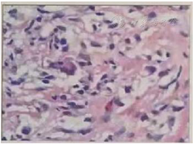

实验室提示白细胞(WBC)16.33×109/L,中性粒细胞比率(NE%)76.7 %,血红蛋白(HGB) 105 g/L,嗜酸性粒性粒细胞0.89×109/L。抗IFN-γ抗体滴度治疗期间三次复查均高于1:100。血T-SPOT试验结果为不确定。HIV(-)。痰涂片找分枝杆菌×3次阴性。右侧颈部淋巴结活检病理高通量宏基因测序检测见波斯分枝杆菌属,序列数352;痰及右侧颈部淋巴结活检组织培养及鉴定提示堪萨斯分枝杆菌生长;右侧锁骨上淋巴结脓液病理高通量测序检测见马尔尼菲蓝状菌感染,序列5149;支冲液高通量测序检测见马尔尼菲蓝状菌,序列1。2022年1月19日右侧颈部淋巴结病理提示其内见胶原纤维及纤维母细胞增生,个别可疑形成不良的上皮样细胞、组织细胞、中性粒细胞、淋巴细胞及浆细胞浸润。抗酸染色见个别阳性杆菌,六胺银、Warthin-Starry及PAS染色(-)(图1)。双侧颈部淋巴结彩色超声(图2、图3);胸部CT(图4、5)。